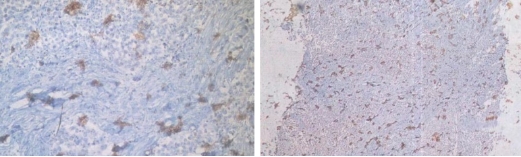

Typical Example:CD34 staining of paraffin-embedded human placental tissue sections:

HRP-directly labeled secondary antibody: Weak positive staining with low background;

Polymer enzyme-labeled secondary antibody: Strong positive staining with clean background and distinct contrast.

Conclusion: Different chromogenic systems yield distinct chromogenic results. Polymer enzyme-labeled secondary antibodies demonstrate higher sensitivity, cleaner background, and more distinct contrast compared to conventional HRP-directly labeled secondary antibodies.